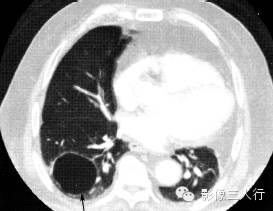

肺脓肿

(图5) |

(A)平扫

(B)增强